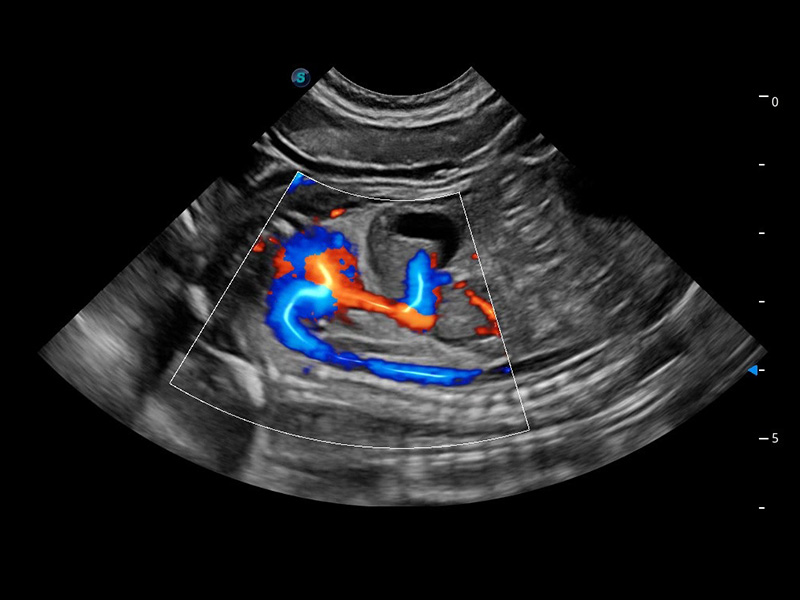

ProPet 60 作為一款高端臺式動物超聲設(shè)備,為動物醫(yī)生的日常診斷提供了一系列貼合動物臨床需求、解決臨床實(shí)際問題的高級成像功能。憑借全系列高清探頭,滿足醫(yī)生對腹部、心臟、生殖、淺表、肌骨等成像的所有需求,切實(shí)幫助您提升檢查效率,提高診斷信心。